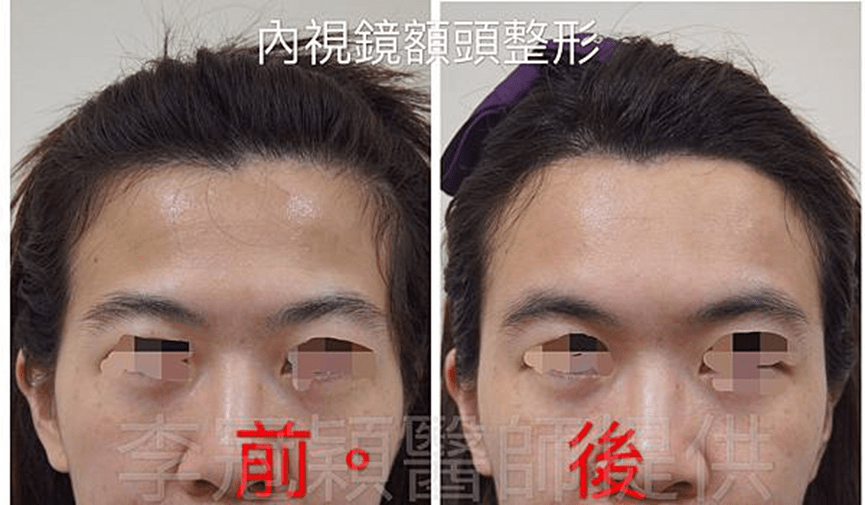

(下圖)內視鏡提眉與太陽穴墊片(相同入口)可一次性完成的無痕跡年輕化,同時改善臉骨過大比例與不對稱。

範例:男性32 歲,太陽穴過窄,經微創內視鏡太陽穴墊片手術改善眉毛下垂外觀。